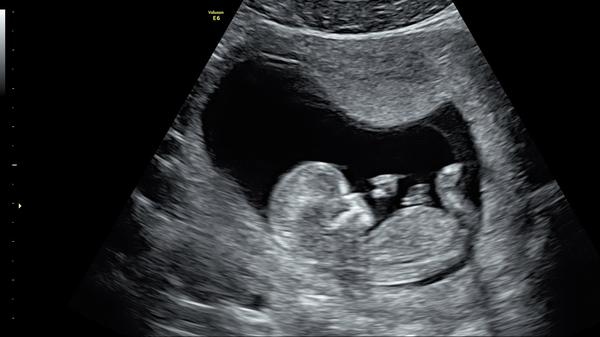

Foto z ultrazvuku. Holčička nebo klučík?

Hezký večer, dnes jsme byli na screeningu v prvním trimestru, paní doktorka nám řekla pohlaví s jistotou 90%, nicméně prý už se takhle jednou sekla, tak by mě, čistě ze zvědavosti, zajímalo, co myslíte vy? Mě to podle toho co jsem na internetu vyčetla sedí s paní doktorkou, ale víte jak, sem baba zvědavá 🙂

takhle to poznala i doktorka, pak mrkla zespodu mezi nožky a ještě si to jakoby potvrdila, ale v 1.trimestru se to poznává právě podle fotky z profilu 🙂

tak paní doktorka říkala, že to bude na těch 90% holčička